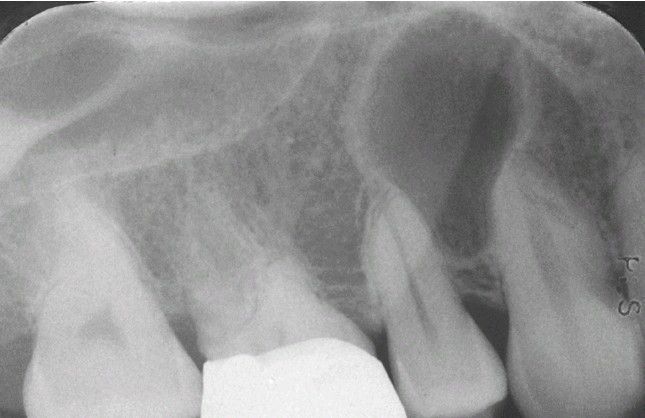

Surgical Ciliated Cyst.

Well-defined radiolucency between vital maxillary bicuspids.

Cyst

Radiograph